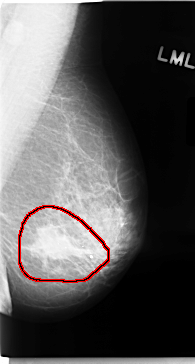

C_0050_1.LEFT_MLO

LEFT_MLO LINES 4720 PIXELS_PER_LINE 2528 BITS_PER_PIXEL 12 RESOLUTION 50 OVERLAY

FILE: C_0050_1.LEFT_MLO.OVERLAY

TOTAL_ABNORMALITIES 1

ABNORMALITY 1

LESION_TYPE MASS SHAPE IRREGULAR MARGINS SPICULATED

ASSESSMENT 5

SUBTLETY 5

PATHOLOGY MALIGNANT

TOTAL_OUTLINES 1

BOUNDARY